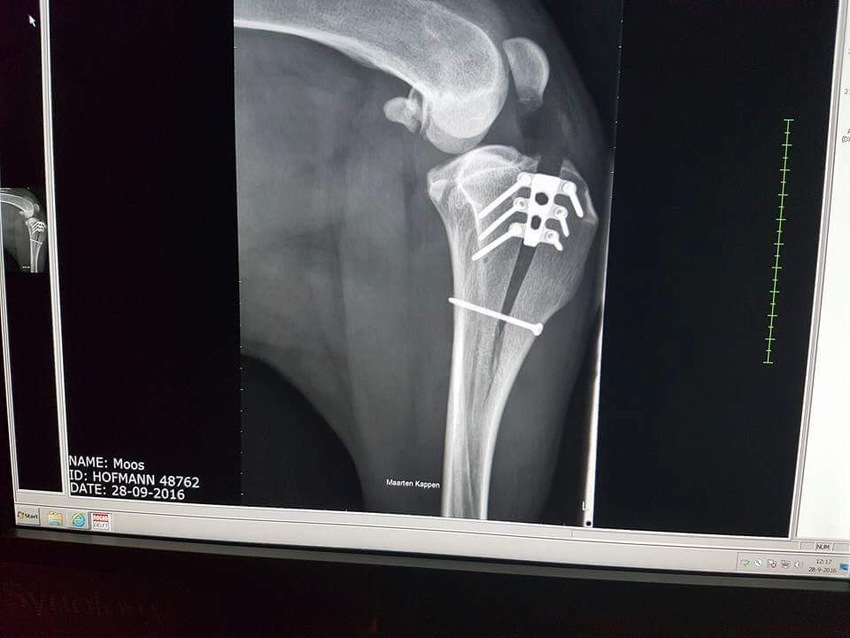

Foto is niet van ogin maar wel van een newfoundlander, deze arts heeft ruime ervaringmet deze methode, vandaar dat ik met spoed daar naar toe gegaan ben......fotoos van ogin worden opgestuurd.....

TTA-Rapid-methodeWerkwijze. TTA-Rapid methode Er wordt een röntgenfoto van het kniegewricht gemaakt. Na de beoordeling van de dierenarts wordt er bepaald welke maat implantaat wordt gebruikt. Vervolgens worden restanten van de oude kruisband en eventueel resten van een kapotte meniscus verwijderd. Deze resten kunnen namelijk de knie flink irriteren. Wanneer de restjes zijn verwijderd kan de dierenarts met speciale chirurgische instrumenten het onderbeen prepareren zodat er ruimte wordt gemaakt voor het implantaat. Nu kan het implantaat worden geplaatst en wordt deze vastgeschroefd. Nabehandeling De eerste drie weken na de operatie moeten we de patiënt aan de lijn uitlaten, alleen voor de noodzakelijke behoeftes. De drie weken erna mag er weer drie keer daags een korte wandeling van 10 minuten worden gelopen. Wildheid en overbelasting gedurende deze periode nog wel voorkomen. Na zes weken volgt eventueel een controle foto om te zien of alles in orde is. Hierna kan de normale activiteiten weer langzaam opgebouwd worden. Voordelen van de TTA-Rapid methode Sneller herstel van het kniegewricht Betere permanente stabiliteit van de knie in vergelijking met oude operatietechnieken Minder ingrijpende operatie Minder kans op complicaties in vergelijking met TPLO, Titanium-implantaten hoeven niet achteraf te worden verwijderd. De TTA-Rapid methode maakt de voorste kruisband overbodig